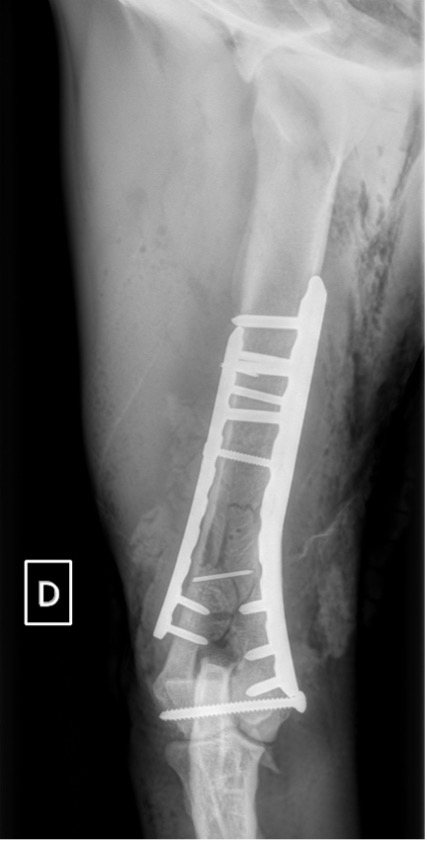

L’avènement récent des plaques anatomiques constitue une nouvelle option dans le traitement de ces fractures : dans l’exemple 3 (chat Ragdoll), une plaque anatomique médiale de 2 mm acceptant des vis de 1,6 et 2 mm a été utilisée seule avec succès.

Exemple 3 :

Figure 9 : Pré-Op

Figure 10 : Opération

Figure 11 : Post-Op Immédiat